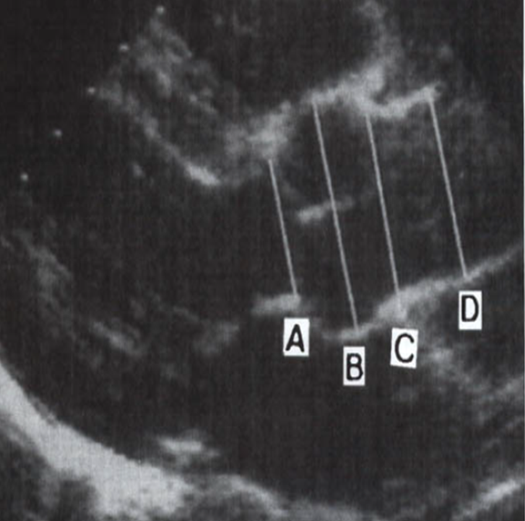

label

A : aortic annulus

B : sinuses of valsalva

C : sinotubular junction

D : ascending ao